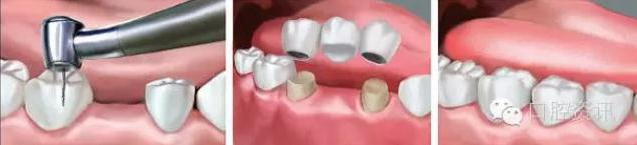

2 . 牙支持式固定義齒

也稱固定橋,是通過固位體與人工牙連接成為一個整體,利用粘結(jié)劑

固定在缺牙間隙兩端或一端的天然牙或牙根上,以修復(fù)缺失牙。這類

義齒需要磨切天然牙(有時需要在局部麻醉下完成),但舒適度好,

無需患者自己取戴,功能和美觀恢復(fù)較好。

7.jpg

圖7. 固定橋